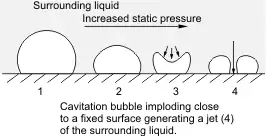

The mechanism of action for sonodynamic therapy is the use of low-intensity ultrasound through the use of focused mechanical waves to create a cytotoxic effect. However, SDT itself is non-thermal, non-toxic, and is able to non-invasively penetrate deep into tissue compared to other delivery methods such as photodynamic therapy. SDT is often performed alongside the use of a sonosensitizer such as porphyrin, phthalocyanines, xanthenes, and antitumor drugs.[17] Ultrasound waves are also classified as acoustic waves, and the effect they have on the tissue of application can be described by a process called cavitation. Cavitation occurs as a specific interaction between ultrasound and aqueous surroundings and causes gas bubbles to break upon exposure to particular ultrasonic parameters, thus promoting penetration of the therapeutic into the biological tissues by generating cavities near the edge of the membrane.[18][1] Cavitation can be broken down into stable and inertial cavitation. In stable cavitation, the oscillation of gas bubbles causes the environmental media to intermix.[1] In inertial cavitation, gas bubbles increase in volume and almost reach their resonance volume, swelling before aggressively collapsing.[1] The implosion of vesicles results in a drastic temperature and pressure change, thereby increasing the cell membrane's permeability to various drugs.[1][19] Microbubbles are created by the acoustic waves from the ultrasound that expand and collapse, releasing energy, bringing the sonosensitizer into an excited state, and generating a ROS. The cavitation of this gas bubble can form the ROS with different methodologies such as sonoluminescence and pyrolysis.[1] Apoptosis results from the formation of ROS and mechanical forces of SDT through membrane disruption in a process called lipid peroxidation. Necrosis is also a potential result of SDT.

Low intensity ultrasound has been shown within past literature to induce apoptotic effects within surrounding cells. It has been found that it is not the initial ROS that causes apoptosis within the cells, but the free radicals within the mitochondria. In a study by Honda et al., it was determined that the mitochondria-caspase pathway is responsible for apoptosis through the increase of intracellular calcium.[1][30] Outside of ROS induced apoptosis, cavitation is another factor involved within apoptosis of surrounding cells. Both cavitation types are able to induce apoptosis through damage to the membrane. Conditions such as frequency, duty cycle, pulse, and intensity can be manipulated to optimize cell death conditions such as necrosis, lysis, or apoptosis.[31][24][32]